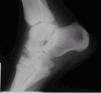

Neuroartropatía diabética